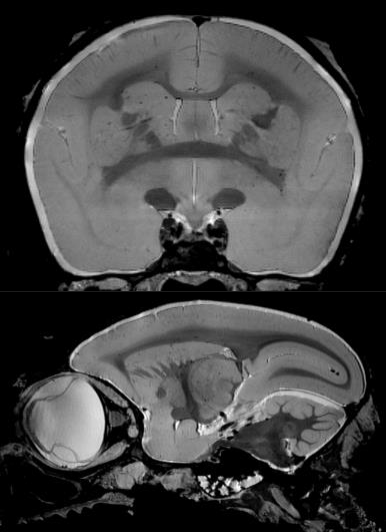

2、功能磁共振成像

功能磁共振成像需要最強(qiáng)的磁場(chǎng),最好的梯度和最穩(wěn)定的系統(tǒng)。布魯克優(yōu)異的梯度系統(tǒng)確保在單次激發(fā)下得到整個(gè)腦部的圖像。功能卓越的勻場(chǎng)單元最大程度地消除平面回波成像幾何形變。特有的頻率和相位穩(wěn)定性保證多次激發(fā)EPI擴(kuò)散張量成像的品質(zhì)。高分辨率的功能磁共振成像可以深入洞察大腦的功能反應(yīng)。

小鼠腦部的功能磁共振成像: